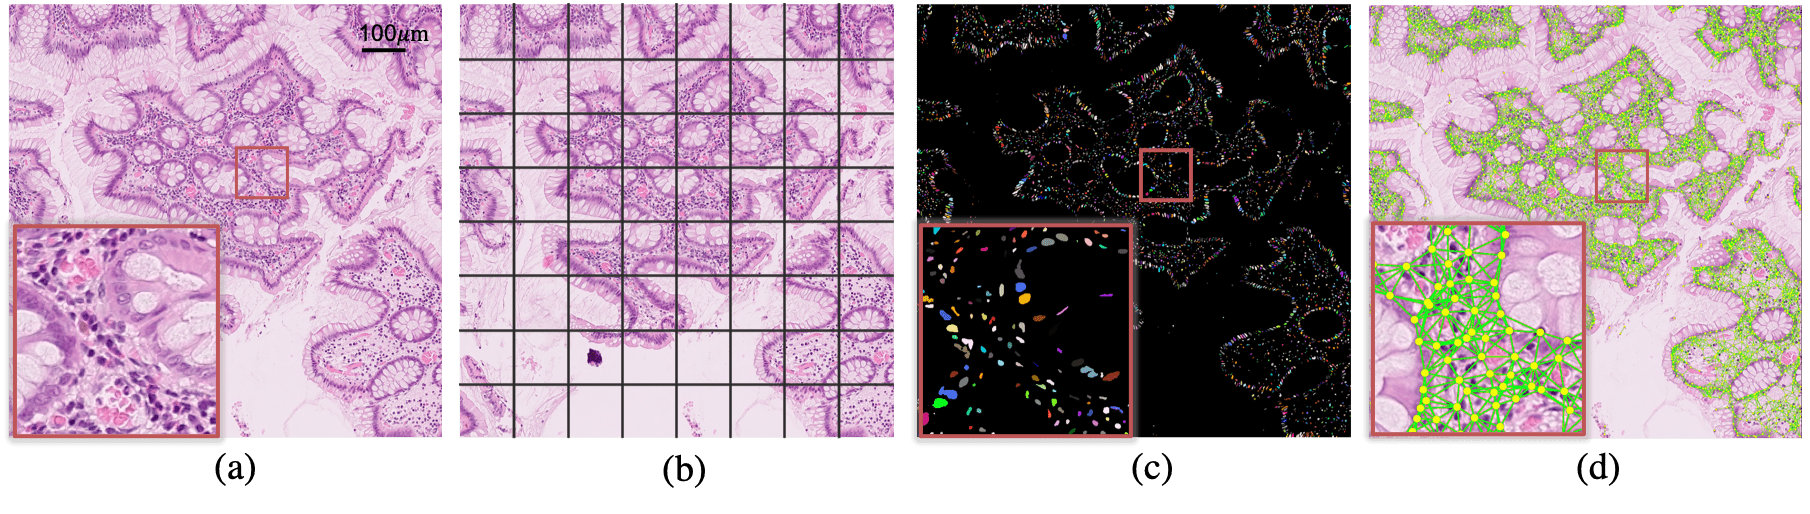

{strip}[Uncaptioned image]

Figure 1: A histology image (a) is typically broken into small image patches (b) for cancer grading. We propose to utilise the cell graph (d) that is built from individual nuclei after segmentation (c) to model the entire tissue micro-environment for cancer grading.